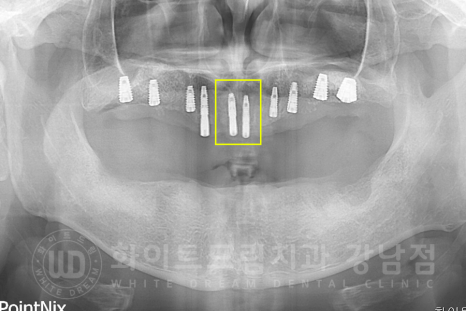

환자분의 x-ray를 보면 대다수의 치아가 없는 상태이고,

그나마 남아있는 치아들도 쓰러져있거나 치아 뿌리만 잇몸뼈에 겨우 매달려있는 상태였습니다.

치주염이 굉장히 심한 상태여서 살릴 수 있는 치아는 없었기에

전악 발치 후 전체 임플란트 치료를 진행하기로 했습니다.

▲ 전악 발치 후 환자분 x-ray 사진입니다. (17.06.03)

▲ 노란색으로 표기된 부분이 1+2차 수술을 동시 진행한 임플란트입니다. (상악)